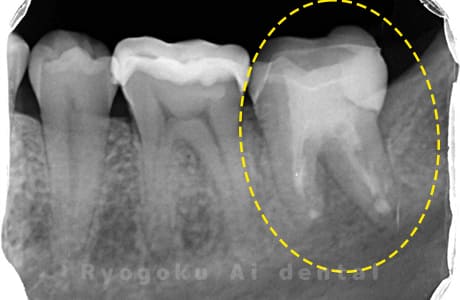

Case04

-

- 原因

- 歯根嚢胞

- 治療内容

- 歯根端切除法

- 治療費用

- ¥110,000

他院で治療した歯が腫れていて、様子を見るように言われたが、なかなか治らない、とのことでご来院された患者さんです。歯根端切除術を行い、腫れもなくなり、経過良好です。

<リスク・副作用>

外科手術のため、術後に出血、痛みや腫れ、違和感を伴います。口腔内の状態によっては適応できないことがあります。歯根端切除で治らなければ抜歯を検討しなくていけない場合もあります。